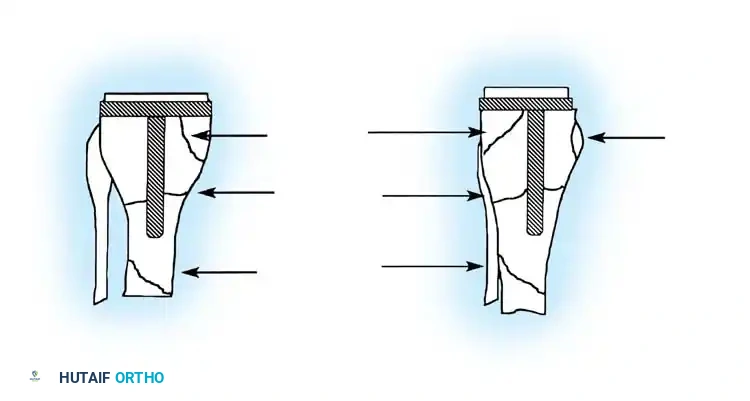

Fig. 6-71 Anatomical locations of tibial fractures associated with total knee arthroplasty.

Tibial periprosthetic fractures (Felix classification) are similarly managed based on the anatomical location of the fracture relative to the stem, the stability of the implant, and the timing of the fracture (intraoperative vs. postoperative).